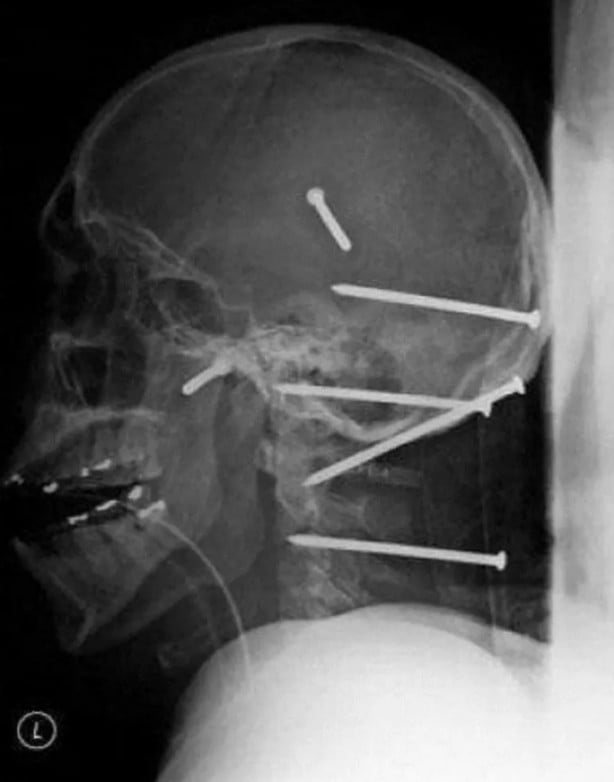

İşte görenleri şaşırtan o röntgen filmleri...